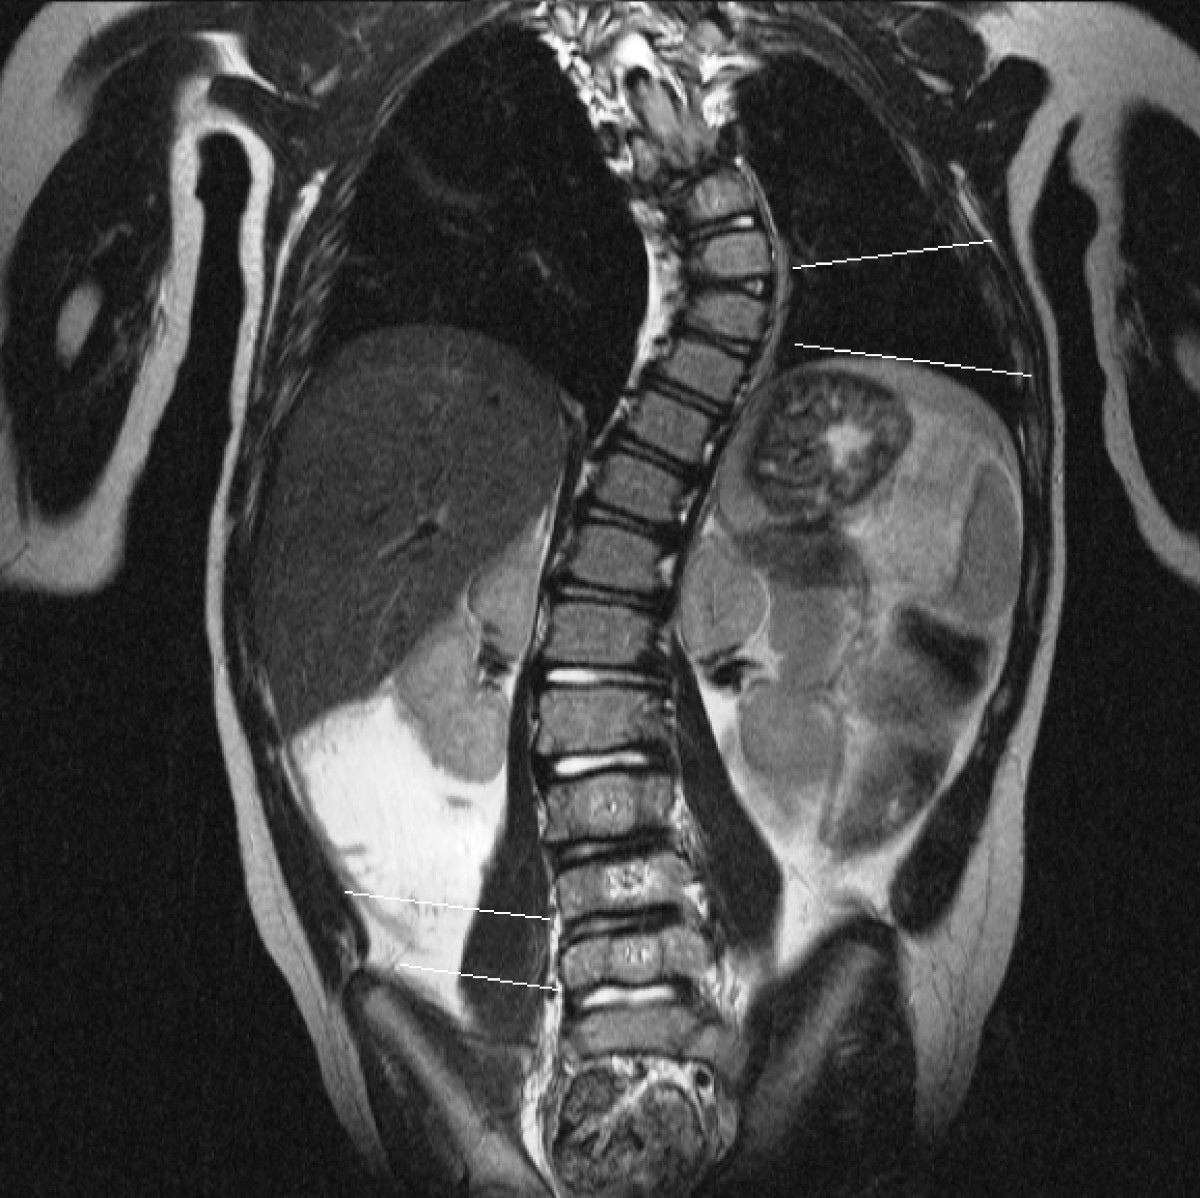

From www.researchgate.net

MRI T2weighted Sequence, Coronal Plane Image. Congenital Scoliosis Vertebral Disc Scoliosis When the cushions wear away, the bones can start to rub. Your spine (backbone) naturally has a slight forward and. Everyone’s spinal disks degenerate over time and is a normal part of aging. Certain neuromuscular conditions, such as cerebral palsy or muscular. Spinal decompression is the relief of pressure on the spinal cord or on one or more compressed nerve. Vertebral Disc Scoliosis.